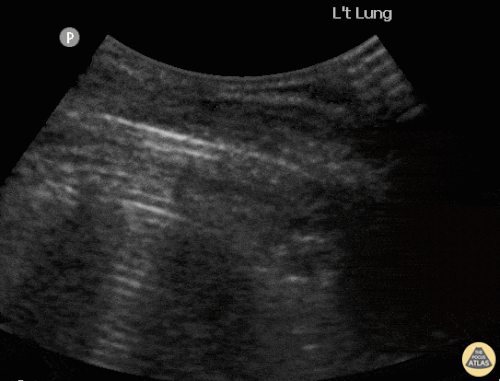

Based on the ultrasound image below, which shock etiologies are least consistent with this finding?

1 pts